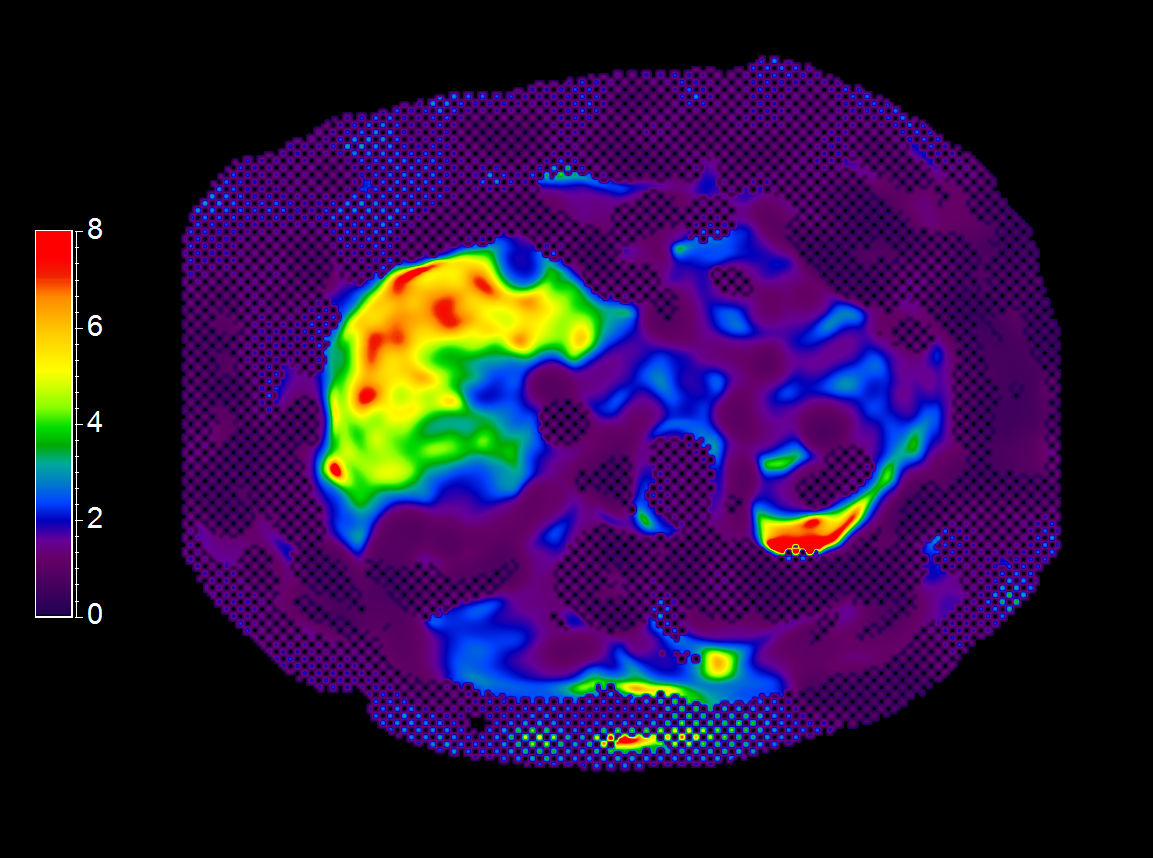

Liver ExamCard including single breath hold 3D mDIXON Quant for non-invasive liver fat quantification of the whole liver with high accuracy (± 3.5%) and reproducibility (± 1.4%)1. And MR Elastography for a non-invasive assessment of differences in tissue stiffness of the liver. Image processing is fully integrated at the scanner with automated calculation of Elastograms, reflecting tissue stiffness in kPa and statistical confidence map for reliability assessment.

MR Elastography (SE-EPI, 4 slices) (Stiffness Map)